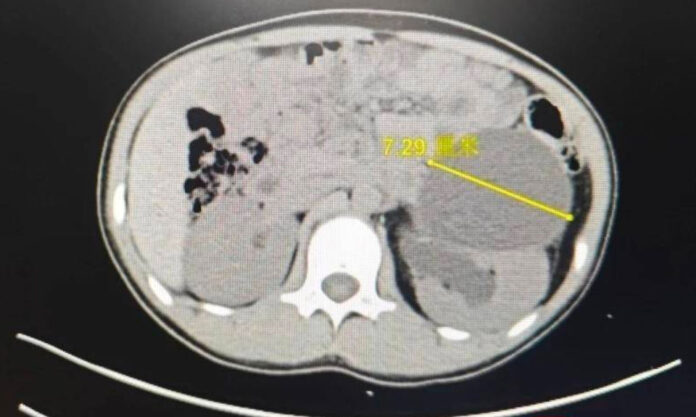

With the 12 year old who lives in Donghai County of Lianyungang in considerable pain, it was found the giant ureter in the her body was actually 15 times larger than the five-millimetre norm for a child. A doctor’s surgery corrected the deformity. Full story (in Chinese) via this link; read the absolute essentials about Lianyungang via this link.

3 Ureters; Teenage Girl’s Physical Mystery in Lianyungang Finally Solved